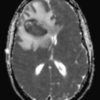

Apxe não

» Thông tin: Nam giới – 35 tuổi.

» Lâm sàng: Đau đầu.